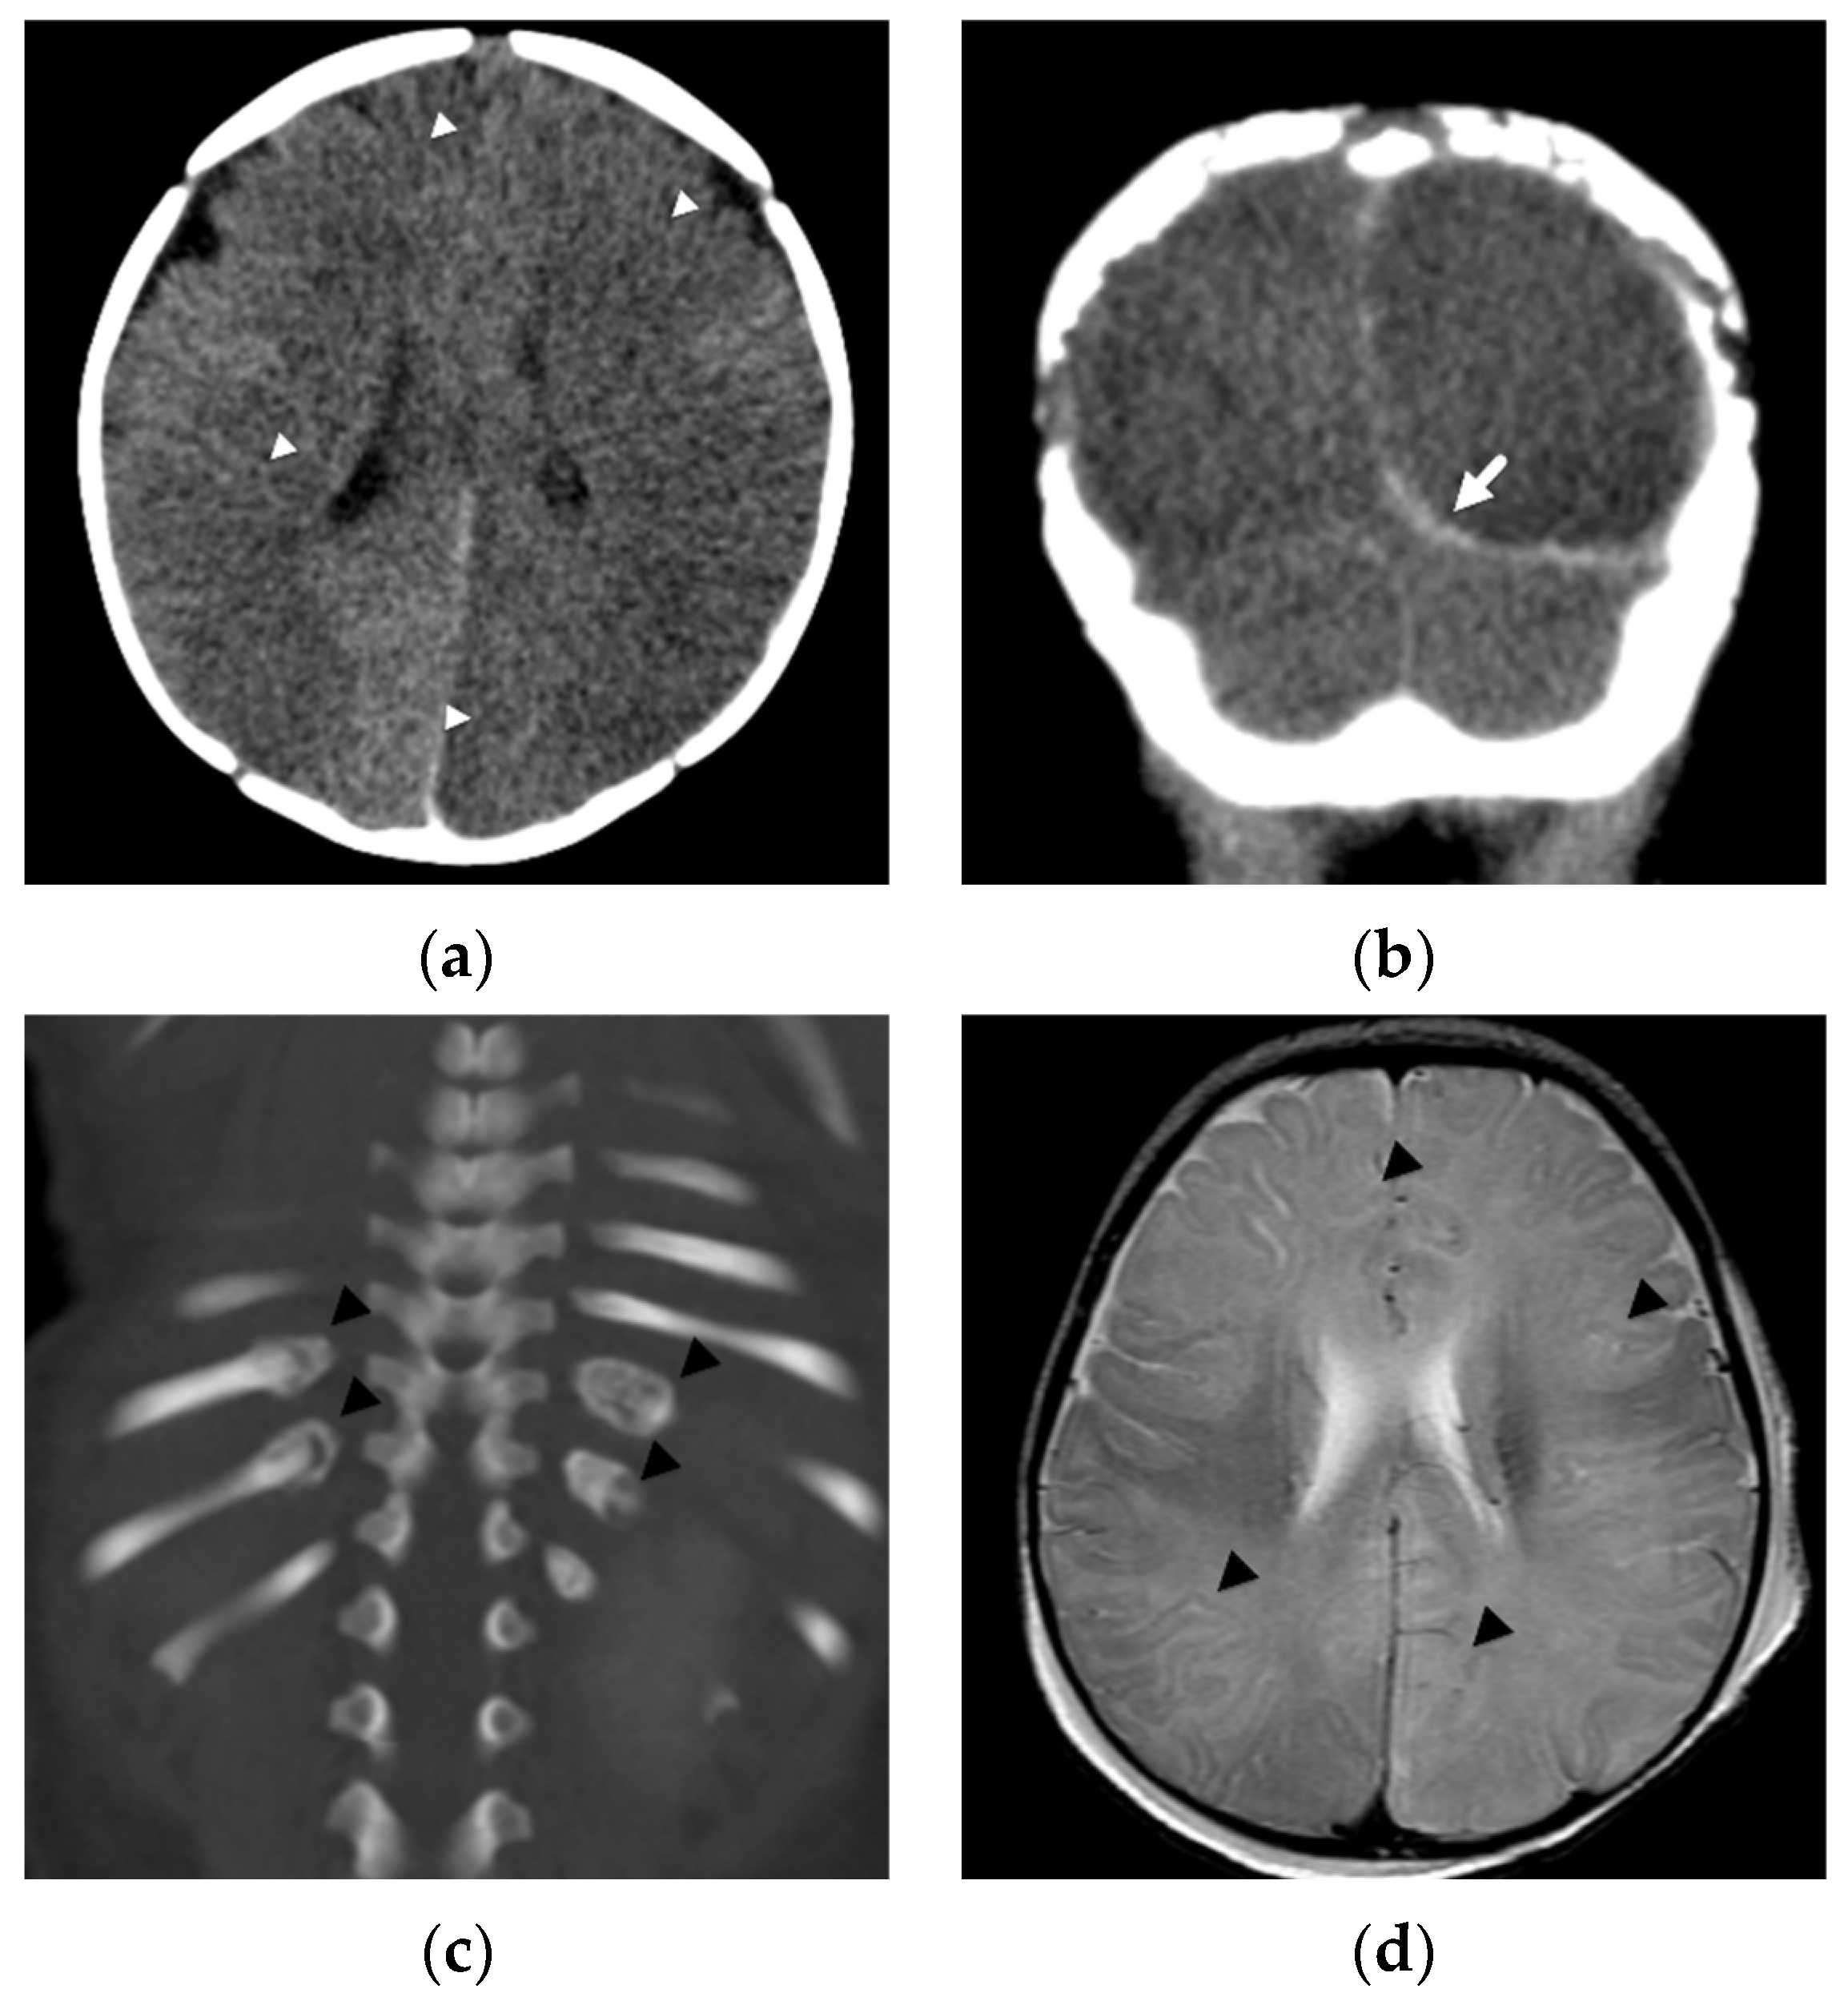

2. Patterns of Diffuse Parenchymal Insults

3. Imaging of Diffuse Insults

4. Focal Parenchymal Insults

5. Imaging Evaluation